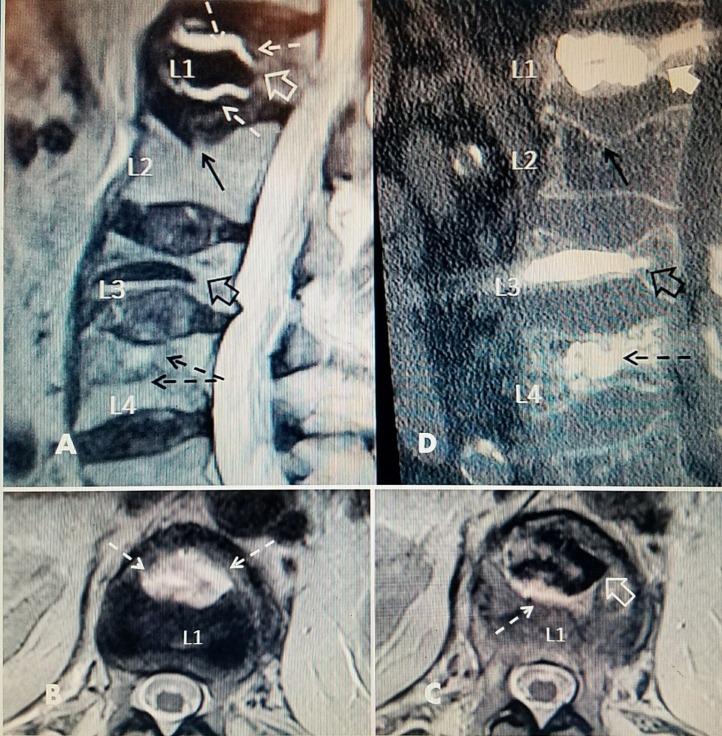

It is well recognized that patients can develop additional vertebral compression fractures (VCF) in an adjacent vertebra or at another vertebral level after successful vertebral augmentation. Factors such as the patient's bone mineral density, post procedure activity, and chronic corticosteroid use contribute to an increased risk of re-fracture or development of new fractures in the first three months after the initial procedure. However, there is a very small subgroup of patients that have unchanged or worse pain after the vertebral augmentation that may indicate continued progression of the treated compression fracture or a recurrent fracture at the previously treated level. This review examines the clinical findings, radiologic signs, and intraprocedural technical failures that may occur during the initial vertebral augmentation that can lead to a progressive fracture in a previously treated vertebra. Causes of failure of the initial vertebral augmentation procedure include inadequate or incomplete filling of the fracture site, the cement missing the actual fracture allowing continued osteoporotic compression, and persistent or worsened intravertebral fluid-filled clefts. The existence of an unfilled intravertebral fluid cleft on preoperative diagnostic studies is the most important indicator of risk for progression as is the later development of fluid at the bone cement interface.

众所周知,患者在椎体强化成功后,可能会在相邻椎体或其他椎体水平发生额外的椎体压缩骨折(VCF)。患者的骨密度、术后活动情况以及长期使用皮质类固醇等因素,会增加初次手术后头三个月再次骨折或发生新骨折的风险。然而,有一小部分患者在椎体强化后疼痛未减轻甚至加重,这可能表明治疗的压缩骨折仍在进展,或者在先前治疗的部位出现了复发性骨折。本综述探讨了初次椎体强化过程中可能出现的临床发现、影像学征象以及术中技术失误,这些情况可能导致先前治疗的椎体发生进行性骨折。初次椎体强化手术失败的原因包括骨折部位填充不足或不完整、骨水泥未填充到实际骨折处,导致骨质疏松性压缩持续存在,以及椎体内持续存在或恶化的充满液体的裂隙。术前诊断研究中存在未填充的椎体内液体裂隙,以及骨水泥界面后期出现液体,是骨折进展风险的最重要指标。